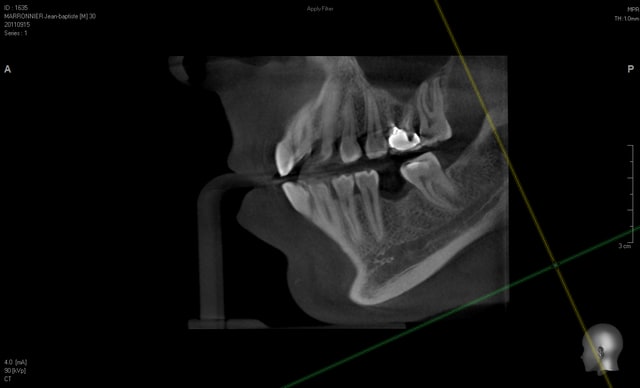

Oui, c'est très simple.

Et mon avis est difficilement objectif maintenant que j'ai l'appareil, mais la qualité est excellente...

voilà des images de tout les jours....